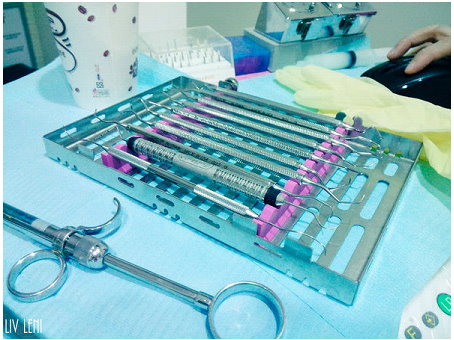

打上麻藥後,開始進行 右邊口腔的牙周刮除術,

雖然看器械好像很可怕,

但因為麻藥的關係,過程中是沒有感覺的,而且相當快速。

牙醫師會 清潔或「刮除」牙齒與牙齦線上下方的牙結石,

此為「牙根刮除術」。

若情況較為嚴重,可能會進行「牙根整平術」,

牙根整平術可使牙齒根部的不規則處變平滑,讓牙菌斑更難沈積。

光用手指觸碰無法得到正確讀數,要利用兩支鈍端的器械,

通常是口鏡及牙周探測器的柄,才能測得牙齒鬆動的程度。